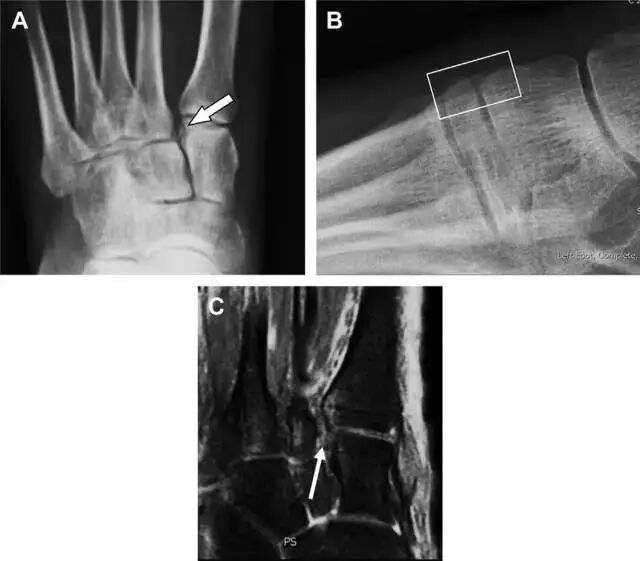

距骨外侧突骨折

距骨外侧突骨折常因踝外翻背屈时,跟骨上外侧面撞击距骨外侧突下缘导致,或偶尔由踝内翻引起,被称为「滑雪板者骨折」。这种骨折只能在踝关节正位片上发现,而且外踝远端表面软组织肿胀往往是一个重要线索(图 4)。

图 4 距骨外侧突骨折。A 正位片示内翻损伤所致的距骨外侧突撕脱性骨折(箭头);B 另一位患者,踝外翻损伤导致典型的「滑雪板者骨折」,X 片上可见一较大的三角形骨折块(方框);C 第二位患者的 MRI 矢状位 T1 加权像示横行骨折(箭头)